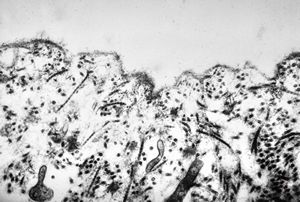

M, 60y. | otitis externa … microbes (fungi?) on the epidermal surface

M, 60y. | otitis externa … microbes (fungi?) on the epidermal surface